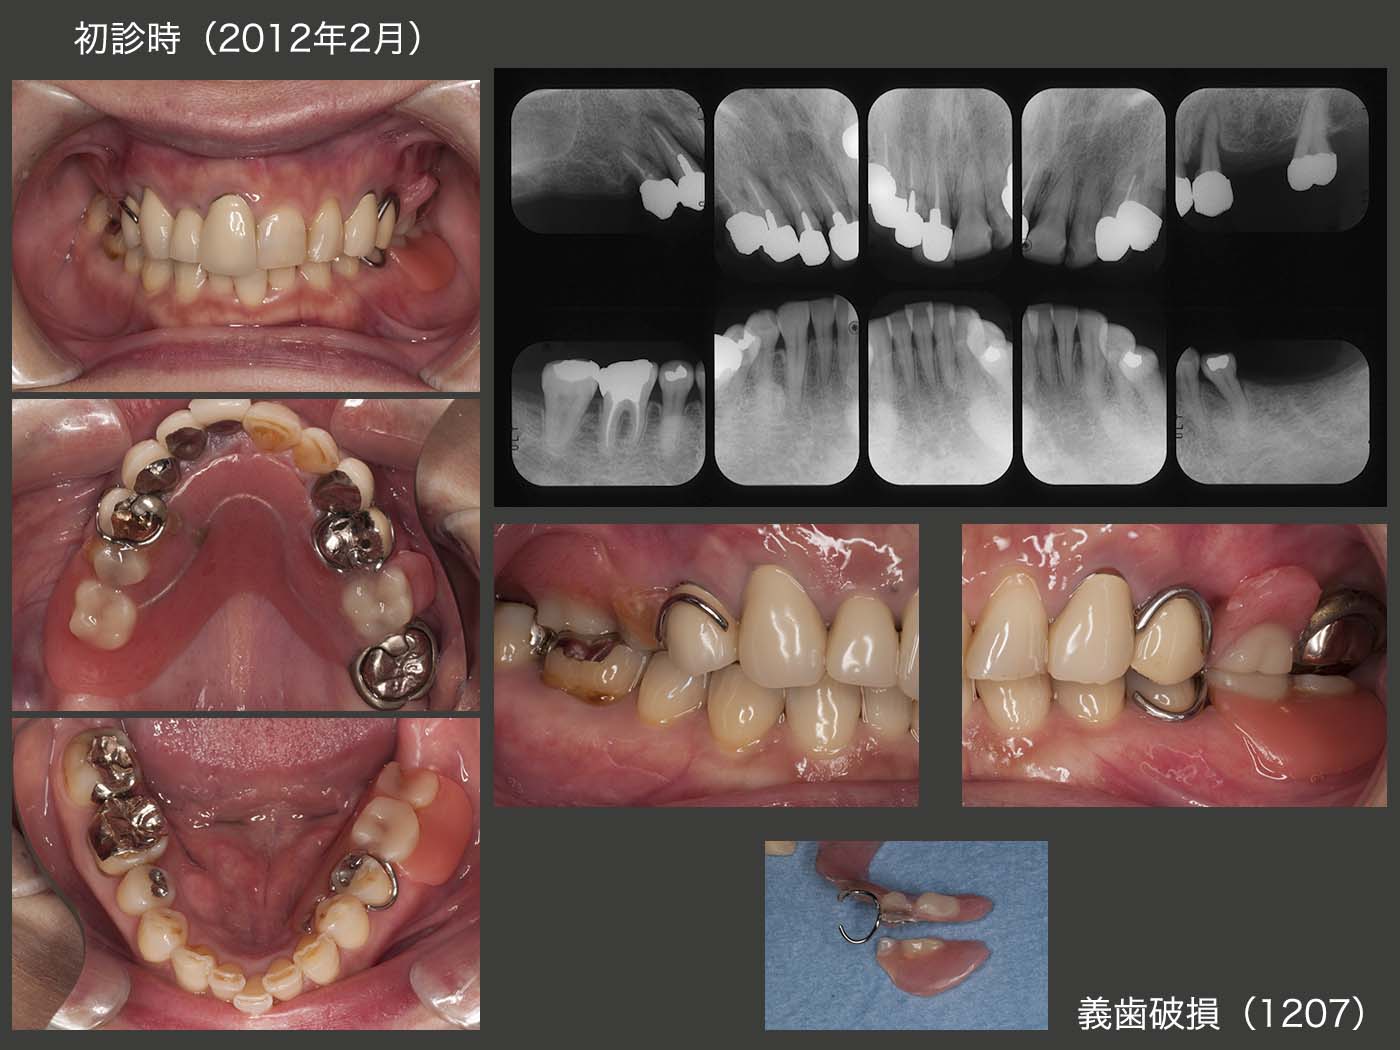

11.移植歯が偏咀嚼主機能歯の場合(症例2)

初診時の右側方面観の写真は,下顎偏心位で撮影された可能性が高いが,2012年7月の中心咬合位での右側方面観では,義歯のスペースが全くない状態であった.右上3は歯根破折しており,抜去した.そこでまず,上顎義歯の維持安定を図るために,右上1,2および左上2,3を支台歯に組み込んだ.動揺の大きかった右上4および抜髄した左上4は残根状にして,力から開放した.なお,右上4は歯周ポケットが最大6mm,左上4は8mm認められた.下顎位を確保するために,暫くの間健全歯である左上1を支台歯として取り込まないようにした.